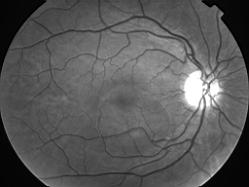

IM000001.jpg